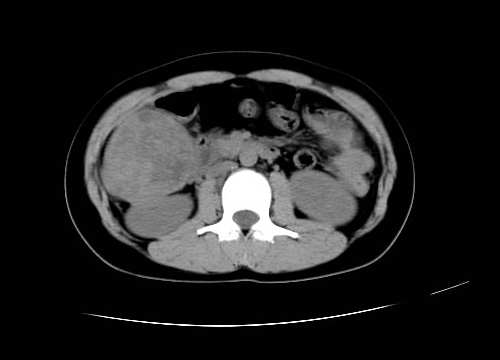

女 16岁  右上腹痛一天,无其他不适

肿块最大径位于十二指肠降段与水平段移行处,并且与肝脏压迹呈“0”形征,可以考虑位于肝外并与胃肠道关系紧密,考虑胃肠道间质瘤(gist)可能较大,须除外神经节起源肿瘤。

肿块与十二指肠关系密切,支持间质瘤诊断.肝脏与结肠均为受压改变.

右下腹巨大肿快,密度不均匀,内见坏死低密度区,边界清楚,与周边胀器明显有分界,未见强化,多考虑来源于间叶组织的良性肿物.

我坚决反对您的观点,该病例定位:横结肠肝曲与升结肠之间的肠系膜及部分肠壁。请看下图:

病灶巨大,少部分向肠腔内生长,大部分向长腔外生长。其密度不均匀,增强显示明显不均匀强化,并见有大片状始终不强化的不规则坏死液化区。虽然病灶中上部形态尚可,病人又如此年轻,但中下部形态、密度、强化特点强烈提示为恶性病灶。综上,我考虑本病例为:恶性胃肠道间质瘤。